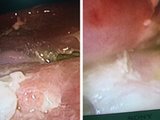

Khi tiếp cận vị trí của dị vật trong tá tràng, BS.CKII Trương Ngọc Nhã, Trưởng khoa Nội soi Bệnh viện Đa khoa Xuyên Á phát hiện dị vật là một chiếc đũa tre dài, một đầu tù cắm sâu vào đoạn D2 - D3 tá tràng gây thủng tá tràng.

Một phương án khác được đưa ra là bệnh nhân sẽ được mổ mở để tiếp cận và lấy dị vật dễ dàng hơn. Nhưng với tinh thần cố gắng hết sức để giúp hạn chế tối đa tổn hại về sức khỏe cũng như tiết kiệm chi phí cho người bệnh, ekip các bác sĩ đã kiên nhẫn dịch chuyển nhẹ nhàng chiếc đũa để lộ ra một đầu đũa. Sau đó, thông qua ống nội soi, các bác sĩ đã đưa vào một đầu dây thòng lọng, thắt chiếc đũa và rút ra qua đường thực quản, miệng.

Chiếc đũa sau khi lấy ra ngoài, đo được chiều dài là 18cm, là loại đũa ăn dùng một lần. Kiểm tra, các bác sĩ phát hiện ra một lỗ thủng lớn, sâu ở tá tràng của người bệnh. Ekip bác sĩ đã tiến hành đặt ống thông dạ dày nuôi ăn đường tĩnh mạch và chuyển bệnh nhân qua Khoa Ngoại tổng quát để tiếp tục theo dõi điều trị vùng tá tràng thương tổn. Hiện tại, sức khỏe anh D. đã ổn định, tình trạng bụng mềm, không đề kháng, chỉ định xuất viện và theo dõi tái khám theo lịch.